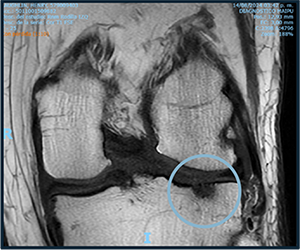

PRE-TREATMENT

AUGUST 13, 2023